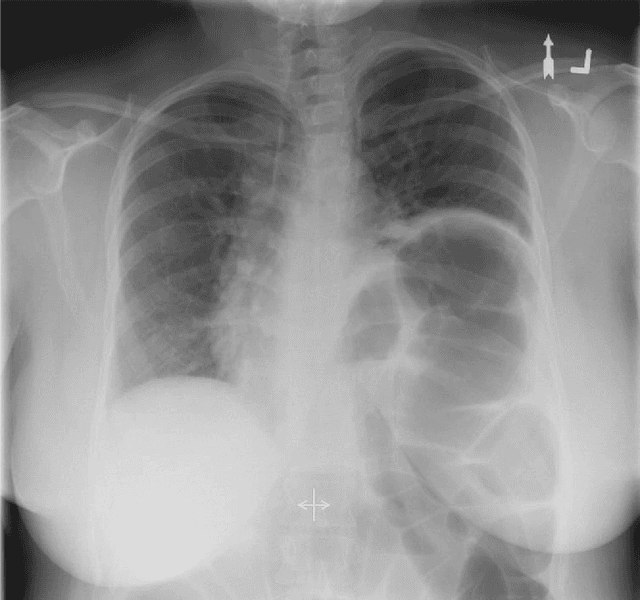

Abstract:The current imaging gold standard for detecting paradoxical diaphragm motion and diagnosing hemidiaphragm paralysis is to perform the fluoroscopic sniff test. The images are visually examined by an experienced radiologist, and if one hemidiaphragm ascends while the other descends, then it is described as paradoxical motion, which is highly suggestive of hemidiaphragm paralysis. However, diagnosis can be challenging because diaphragm motion during sniffing is fast, paradoxical motion can be subtle, and the analysis is based on a 2-dimensional projection of a 3-dimensional surface. This paper presents a case of chronic left hemidiaphragm elevation that was initially reported as mild paradoxical motion on fluoroscopy. After measuring the elevations of the diaphragms and modeling their temporal correlation using Gaussian process regression, the systematic trend of the hemidiaphragmatic motion along with its stochastic properties was determined. When analyzing the trajectories of the hemidiaphragms, no statistically significant paradoxical motion was detected. This could potentially change the prognosis if the patient was to consider diaphragm plication as treatment. The presented method provides a more objective analysis of hemidiaphragm motions and can potentially improve diagnostic accuracy.